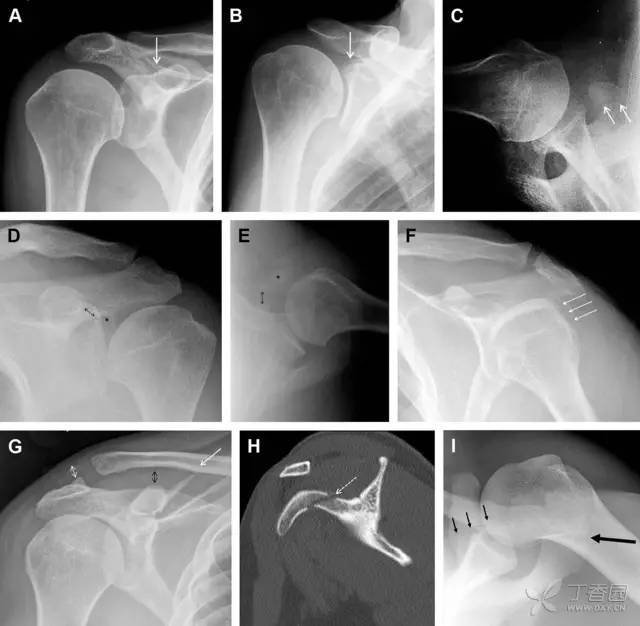

27 肩峰骨折

肩峰骨折为高能量损伤,多由直接*力暴**导致,好发于中青年患者,多伴有肩关节其它结构损伤。有必要拍摄 Rockwood 位(前后位片,X 线束尾倾),特别有利于显示肩峰下部及肩峰下间隙。

图 5 肩峰骨折。内旋位前后位(A)片上,骨折线几乎被喙突完全遮挡, 但是在标准前后位(B)和腋位(C)片上可见骨折线

28 骨折伴盂肱关节不稳

肩关节是最容易脱位的关节之一,肩关节脱位常伴随其它结构的损伤,如血管神经损伤、肩袖损伤、盂唇损伤、Bankart 损伤等。脱位本身诊断往往是明确的,容易被忽略的是其继发的伴随损伤。

需要仔细评估肱骨头、大结节、关节盂边缘、肩峰、喙突等结构。典型的 X 线投射角度包括:内旋位前后位片、外旋位前后位片(Grashey 位)、侧位(肩胛骨 Y 位)、腋位片以及改良腋位片。

图 6 肩关节前脱位伴有 Hill–Sachs 和 Bankart 损伤:(A~C)肱骨头后外侧撞击骨折,白色箭头所示为骨折的内侧边界;(A)内旋位前后位片,(B)「V」形压缩骨折的下边界(虚线短箭头),(C)Garth 位(轴向投影)示 Hill–Sachs 损伤(虚线和实线折箭头),特别是对骨性 Bankart 损伤的诊断有帮助。(D、E)MRI 进一步证实了损伤

图 7 肩关节后脱位伴有反 Hill–Sachs 损伤。(A)外旋位前后位片可见一硬化带(黑箭头),此「凹槽征」与肱骨头关节面平行;(B)腋位片进一步证实了骨折的存在